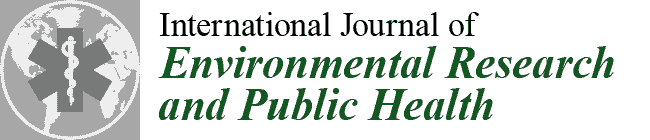

2.2. Experimental Procedure